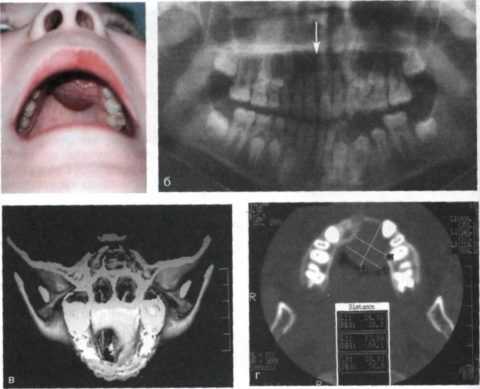

- Рентгенограмма (ортопантомограмма) — на двухмерном снимке видна опухоль с характерными признаками амелобластомы (поражение в виде мыльных пузырей), что позволяет предположить этот диагноз.

- КЛКТ (конусно-лучевая компьютерная томография) — трёхмерный снимок даёт больше информации о положении опухоли в костной ткани, её размерах и строении. Но даже с помощью этого метода можно поставить лишь предварительный диагноз [2][3] .

- МРТ (магнитно-резонансная томография) — покажет патологию в мягких тканях.

- Цитологический и гистологический метод — пункция и трепан-биопсия.